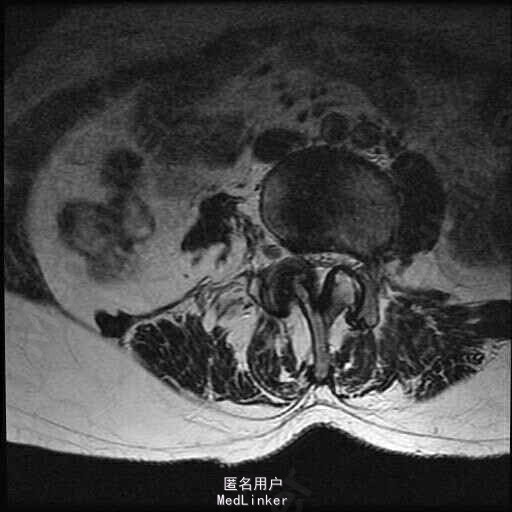

查体:脊柱侧弯,上肢无麻木,疼痛感觉异常,腰部右侧疼痛,右下肢及右臀部疼痛,麻木感。双侧肌力及肌张力可,膝腱反射(+),踝反射(+),病理征(—),直腿抬高试验。右侧40度,左侧55度。 辅助检查:腰椎x线片:腰椎侧弯,腰椎退行性改变,L5椎体略行前滑脱 脊柱全长:胸腰段呈S形,L5椎体向前滑脱,L3椎体略变扁,颈胸腰椎退行性改变 MRI:脊柱侧弯,L2-3,L3-L4,L4-L5,L5-S1椎间盘突出,相应节段椎管狭窄

诊断:腰椎侧弯,腰椎椎管狭窄 治疗:手术矫形:早期侧路减压融合,后期再行后路固定。